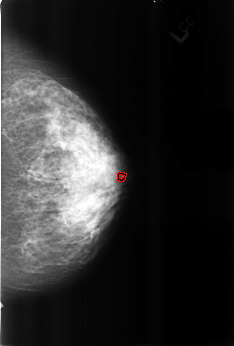

B_3168_1.RIGHT_MLO

FILE: B_3168_1.RIGHT_MLO.OVERLAY

TOTAL_ABNORMALITIES 2

ABNORMALITY 1

LESION_TYPE CALCIFICATION TYPE COARSE DISTRIBUTION N/A

ASSESSMENT 2

SUBTLETY 4

PATHOLOGY BENIGN_WITHOUT_CALLBACK

TOTAL_OUTLINES 1

BOUNDARY

ABNORMALITY 2